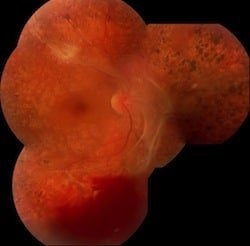

Figura 3. Proliferación vítreo retinal (PVR) con membranas pre retinales, desprendimiento de retina total y desgarros retinales.